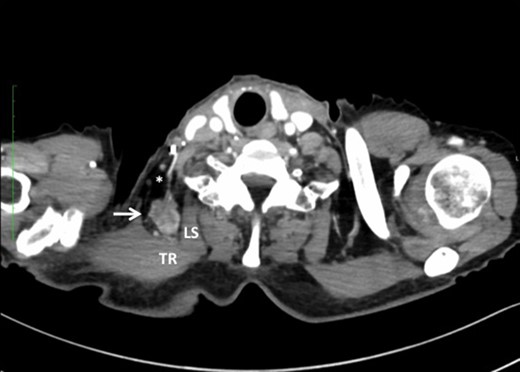

A 76-year-old male underwent screening endoscopy because of a history of gastrectomy for cancer, which showed a superficial and protruding tumor in the mid-thoracic esophagus. Histological examination of the biopsy specimen confirmed well-differentiated squamous cell carcinoma. A computed tomography (CT) scan of the neck, chest and abdomen showed no evidence of metastatic disease. The tumor was clinically staged as T1bN0M0 according to the American Joint Committee on Cancer [1]. He received concurrent chemoradiotherapy at a dose of 60 Gy with low-dose 5-fluorouracil. Four months after completion of chemoradiotherapy, however, the primary tumor relapsed with mediastinal LNM and right SCNM. Right transthoracic esophagectomy with mediastinal and right cervical lymphadenectomy was performed as a salvage treatment. Two months after esophagectomy, a right neck tumor developed that was palpable at the posterior triangle, close to the anterior border of the trapezius muscle. A CT scan of the neck showed a heterogeneously enhanced tumor 25 mm in diameter located between the trapezius muscle and the levator scapulae muscle (Fig. 1). En bloc dissection of the adipose tissue including the tumor and the transverse cervical artery was performed. Histological examination revealed that 5 of the 22 retrieved lymph nodes had metastatic squamous cell carcinoma. The patient received adjuvant radiotherapy of 50.4 Gy to the area of dissection; however, died of pneumonia 11 months after metastasectomy, with locally recurrent disease that invaded right brachial plexus.

Note that the transverse cervical vessels (*) were involved in the tumor (arrow). TR, trapezius muscle; LS, levator scapulae muscle.